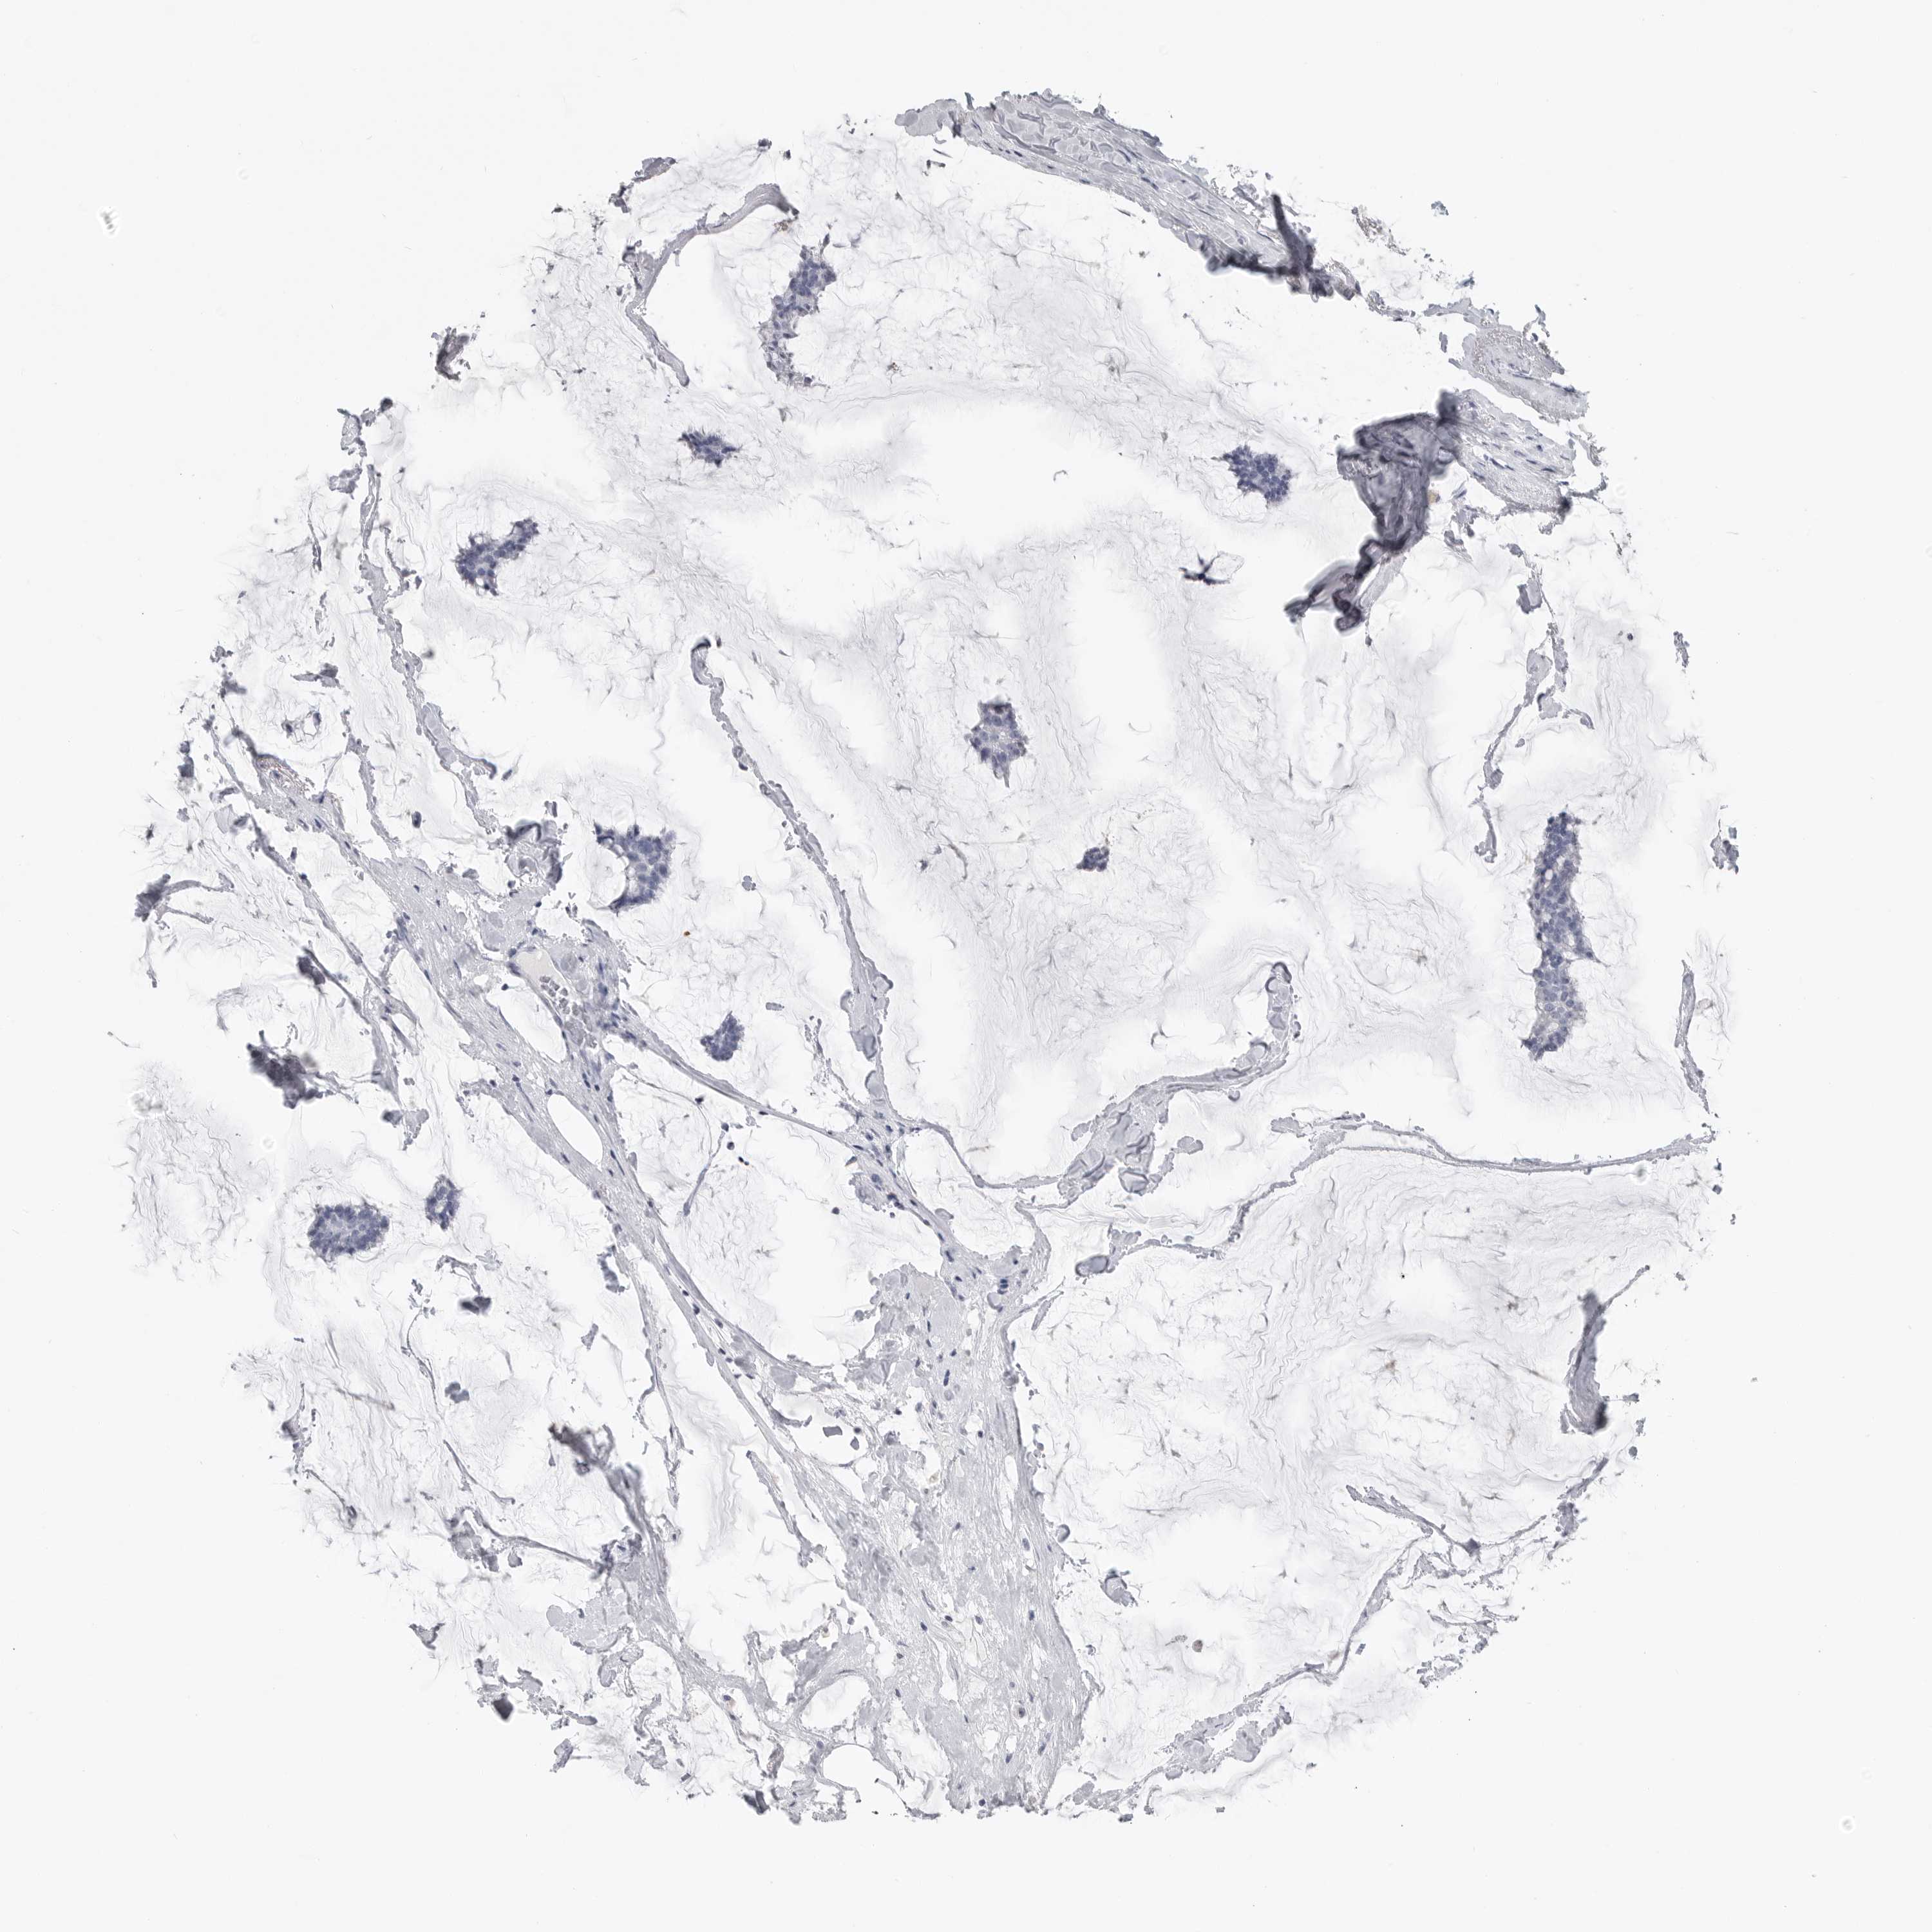

BRCA TCGA BRCA VALIDATION PROTEIN EXPRESSION

Breast cancer

Human cancer